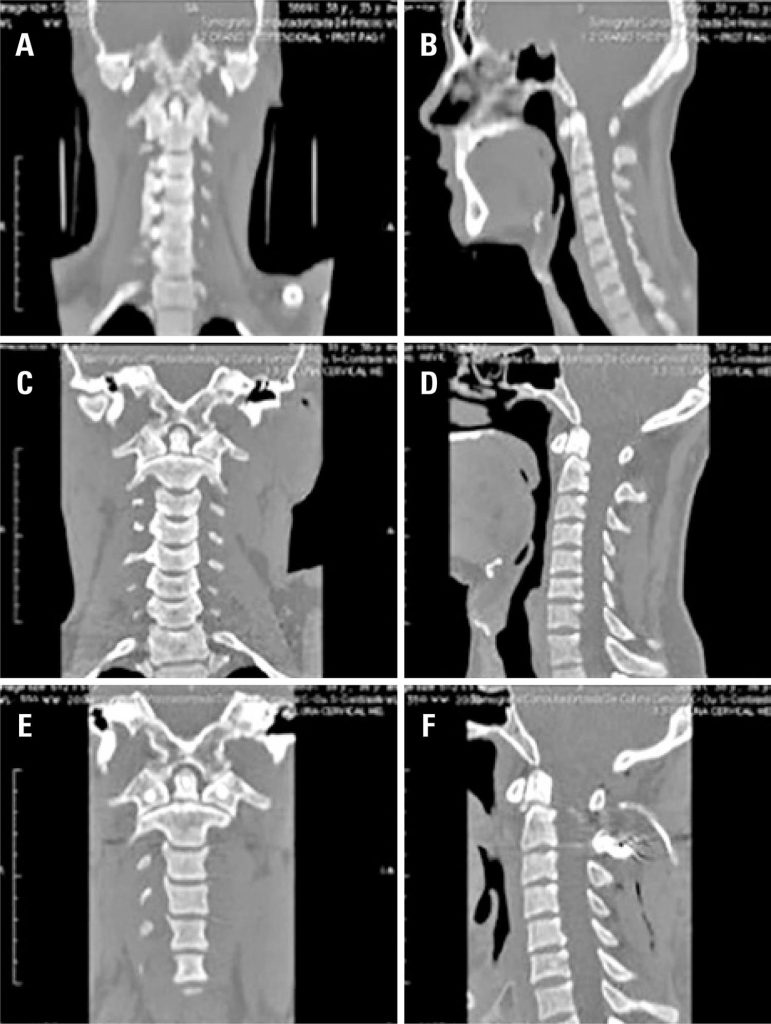

Foram analisados 37 pacientes, 73% eram do sexo masculino e a média de idade foi de 41,7 anos. Inicialmente 32% dos pacientes foram submetidos a tratamento cirúrgico, e 68% foram submetidos a tratamento conservador. Sete pacientes (29%) do grupo conservador foram submetidos posteriormente à cirurgia. No grupo cirúrgico, houve sete casos de fratura de odontóide tipo II, dois casos de fratura de elementos posteriores do áxis, um caso de luxação C1-C2, um caso de deslocamento occipito-cervical e um caso de fraturas de C1 e C2 e luxação facetária. Um paciente apresentava déficit neurológico, melhorando após o tratamento. Houve duas complicações pós-cirúrgicas, uma fístula liquórica e uma infecção de ferida operatória (reabordada). No grupo conservador, predominaram as fraturas do odontóide (oito) e dos elementos posteriores de C2 (cinco). Em dois casos, havia também fraturas em outros segmentos da coluna. Nenhum dos pacientes deste grupo apresentou deterioração neurológica.

As lesões da junção craniocervical são raras, sendo mais frequentes as fraturas do odontóide e dos elementos posteriores do áxis. Nossos resultados recomendam o tratamento cirúrgico precoce para os pacientes com fraturas do odontóide tipo II e lesões ligamentares, e tratamento conservador para os demais pacientes.